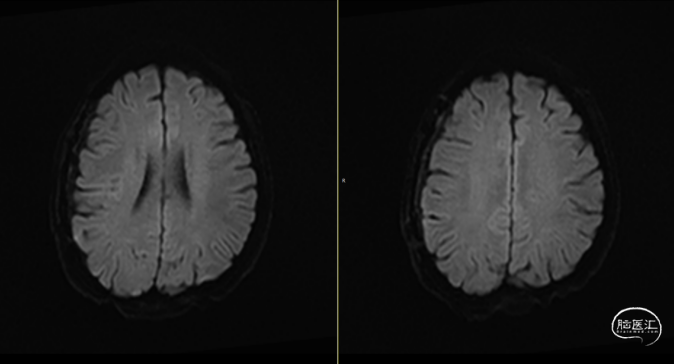

2024-07-21 08:58:55术后58天复查(如上图)。

术后58天颅脑磁共振平扫(如上图):右侧额顶颞部见斑片状异常信号,呈片状T1WI低、T2WI稍高信号影,T2FLAIR呈稍高信号,边界清,右侧额顶颞叶脑组织受压,DWI(b=1000)呈混杂高信号,相应ADC呈混杂高信号影。